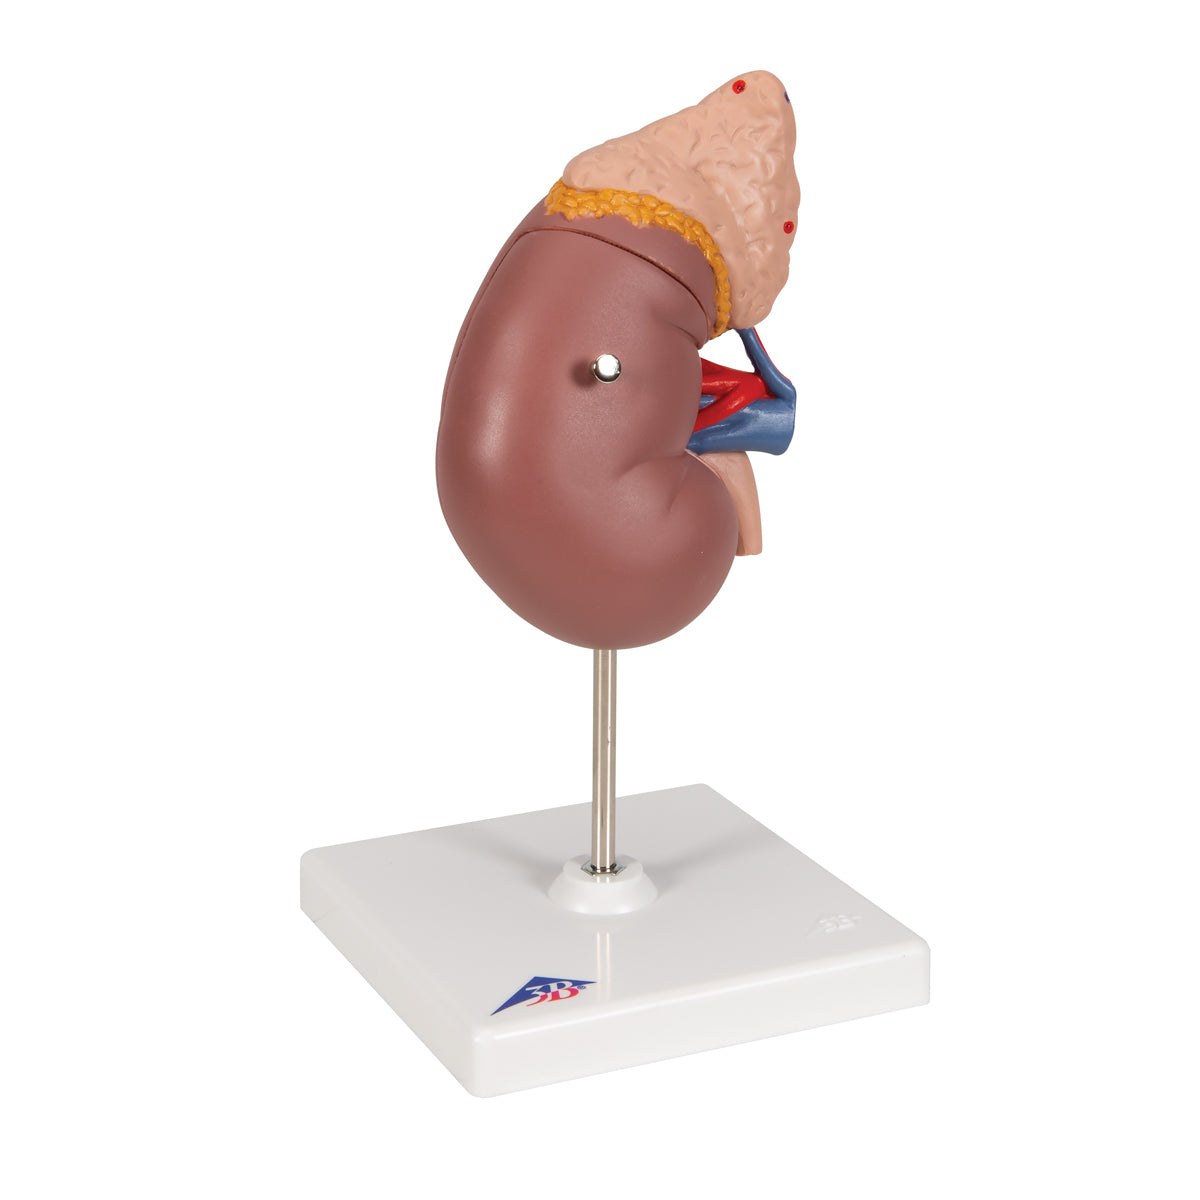

El riñón con glándula adrenal, en 2 piezas

El riñón con glándula adrenal, en 2 piezas

Este modelo presenta:

• El riñón con glándula adrenal

• Conductos renales y adrenales

• Parte superior del uréter

La parte delantera del riñón es desmontable para poder demostrar la corteza de la médula y los conductos así como la pelvis renal. Sobre base desmontable.

- Peso 0.47 kg

- Dimension 20 x 12 x 12 cm